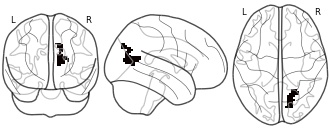

"description": "Multi-modal analysis in BPD. Brain regions exhibiting smaller gray matter and decreased activation during emotion processing in BPD compared to healthy controls. Note: Results were thresholded at p<.0025. Note2: Results were updated (see Erratum for this publication).",